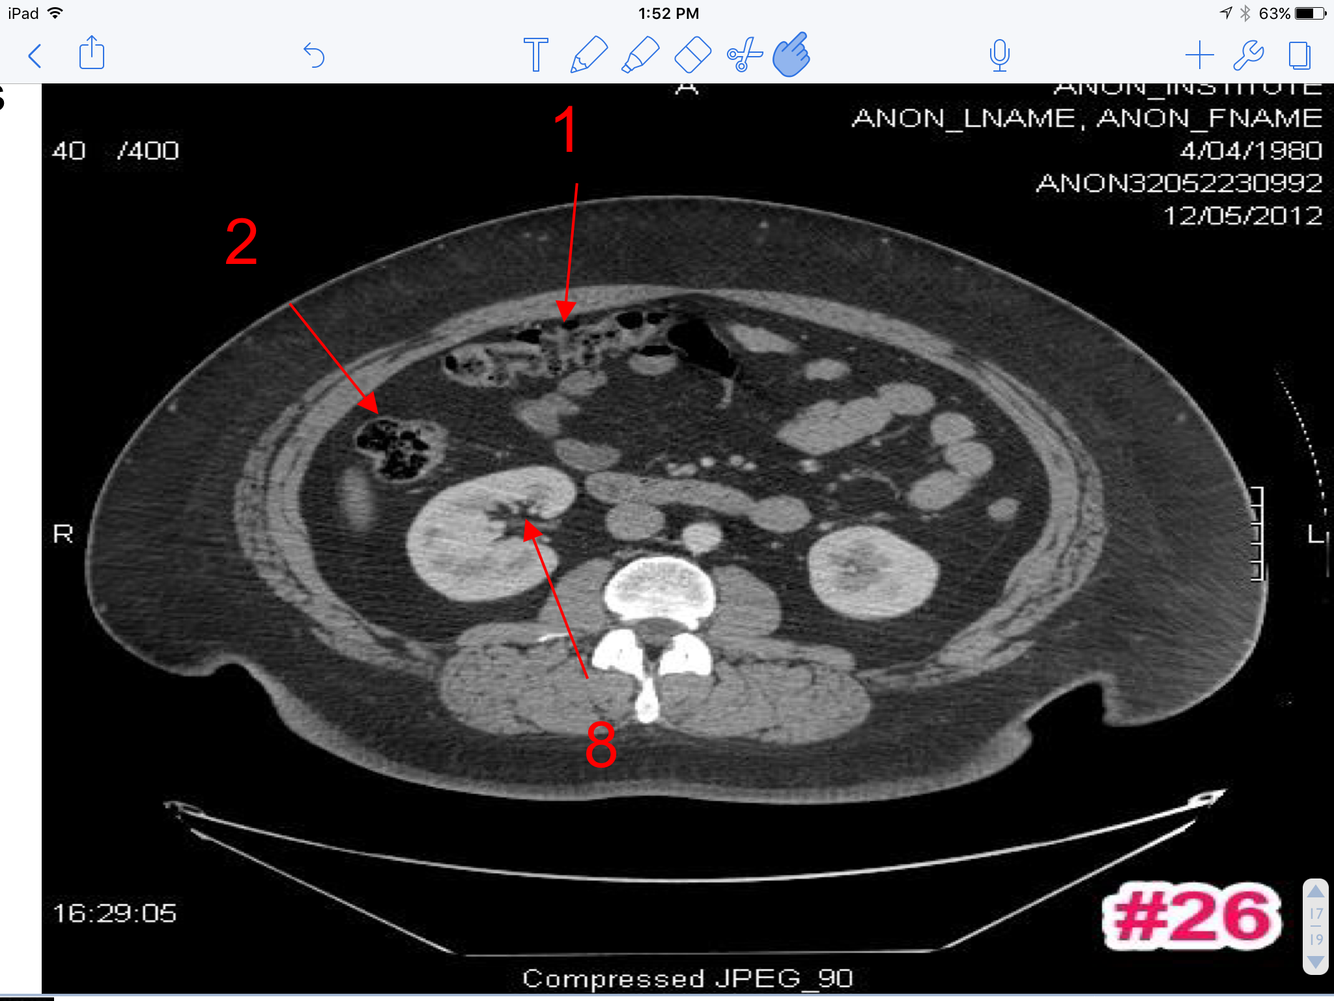

16

A

1. Transverse colon

2. Ascending colon

3. Rt renal pelvis